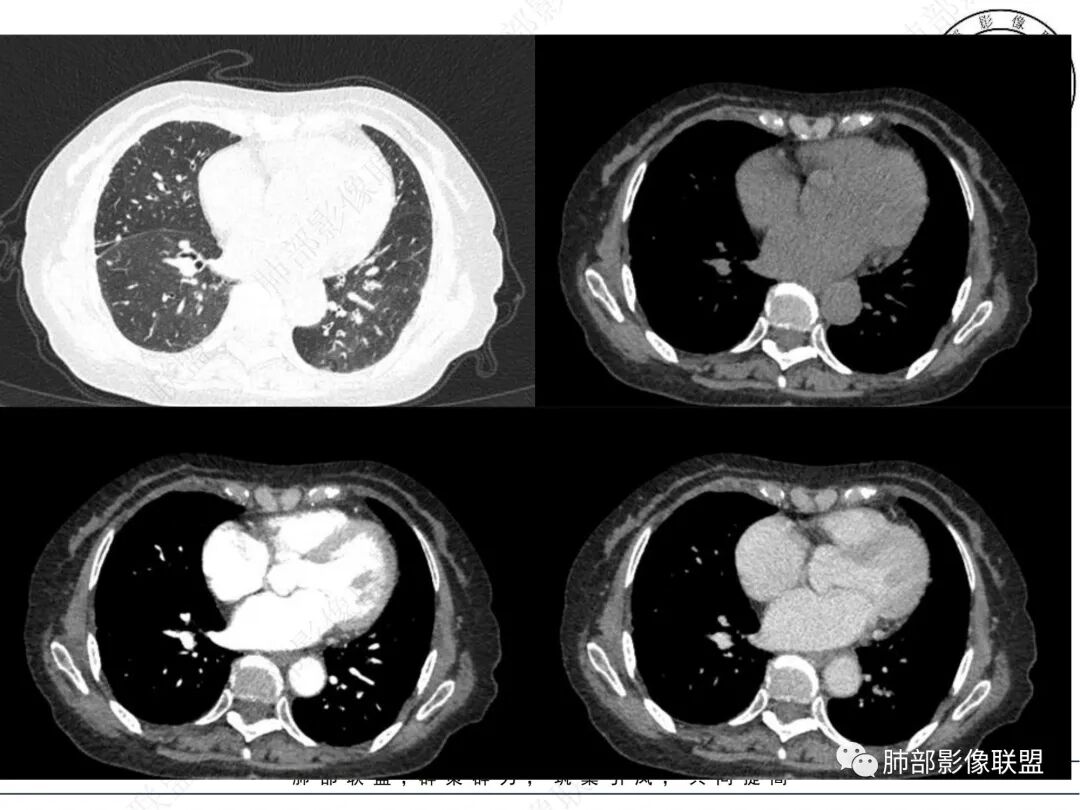

2. CT示右肺上叶多发斑片状实变影,结节影,集群散落,夹杂条索影,边界可分辨,有沿支气管血管束分布趋势,可见树芽征。病灶新旧不等、密度不均。右上叶支气管壁不均匀节段性增厚狹窄,斑点状钙化。纵隔旁部分肺组织含气不良,并显示轻度扩张支气管。病灶邻近胸膜增厚,轻度强化。

4.纵隔多发增大淋巴结,部分融合、钙化。

成簇分布斑片影、结节影、树芽征,边界较清楚,新旧不等,节段性支气管壁增厚伴钙化,管腔狭窄,纵隔及肺门淋巴结增大钙化等都较符合“继发性肺结核、支气管内膜结核”诊断。

老年女性患者应当警惕基础疾病办法新生物的可能性,如常见的肺腺癌等,须仔细甄别有无密度相对均匀的分叶状的磨玻璃或实性密度结节影,以及其他与众不同强化病灶,尤其应当重视复查对比。